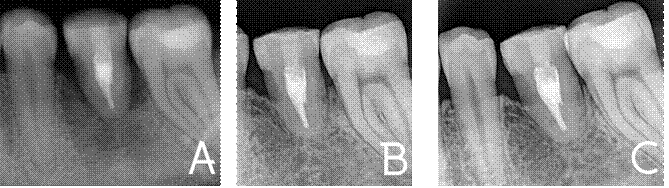

A los 4 meses se observó una excelente formación de hueso cortical y

del ligamento periodontal (Figura 7A), lo que continuó mejorando a los 12

(Figura 7B) y 18 meses (Figura 7C) evidenciando una completa integración

fisiológica entre el ligamento periodontal y hueso, no se observó reabsorción

ósea ni signos de inflamación o infección.

Figura 7.

Radiografías de control A) 4 meses. B) 12 meses. C) 18 meses.